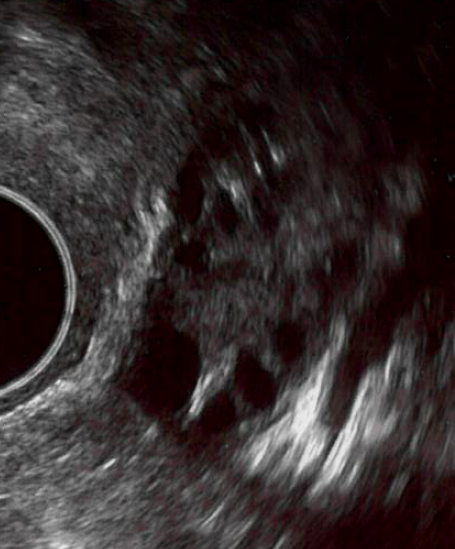

Figuur 2. Eierstok aan begin van de cyclus met kleine eiblaasjes en eierstok met dominant eiblaasje.